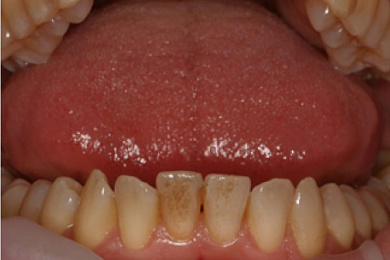

Результат лечения